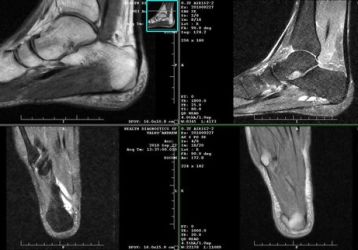

Визуализирующие возможности МРТ голеностопного сустава и стопы

МРТ голеностопного сустава: что это такое, что показывает, цена и особенности проведения. Список диагнозов ведущих к болевым ощущения в голеностопе.